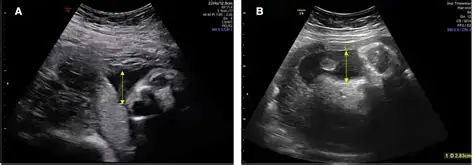

3. Amniotic Fluid Assessment Explained: AFI vs DVP Technique by Dr. Ekta Mishra

A must-know topic for radiology and fetal medicine, explained with complete conceptual clarity.

• Before 16 weeks vs after 16 weeks concept

• Role of fetal kidneys in fluid production

• Link with lung development & oligohydramnios